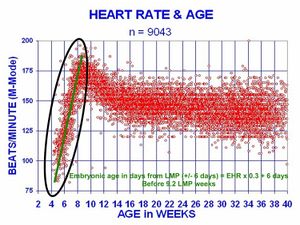

تبدأ ضربات قلب الجنين البشري بعد حوالي 21 يوما من الحمل، أو بعد خمسة أسابيع من آخر فترة طمث طبيعية، وهو التاريخ الذي يُستخدم عادة لتحديد تاريخ بداية للحمل في الطب. وينشأ إزالة الاستقطاب الكهربائي الذي يحفز انقباض الخلايا العضلية للقلب بشكل عفوي داخل الخلية العضلية نفسها. يبدأ نبض القلب في مناطق تنظيم ضربات القلب وينتشر إلى بقية القلب من خلال مسار التوصيل. وتتطور خلايا منظم ضربات القلب في الأذين البدائي والجيب الوريدي لتشكيل العقدة الجيبية الأذينية والعقدة الأذينية البطينية على التوالي. وتُطوِر الخلايا الموصِلة حزمة هيس وتحمل إزالة الاستقطاب في جزء القلب السفلي.

يبدأ القلب البشري في النبض بمعدل قريب من الأم، حوالي 75-80 نبضة في الدقيقة. ثم يسرع معدل ضربات القلب الجنينية خطيا للشهر الأول من النبض، بالغًا ذروته عند 165-185 نبضة في الدقيقة خلال وقت مبكر من الأسبوع السابع (في وقت مبكر من الأسبوع 9 بعد آخر فترة طمث). ويكون هذا التسارع قرابة 3.3 نبضة في الدقيقة في اليوم الواحد، أو حوالي 10نبضات في الدقيقة كل ثلاثة أيام، بزيادة قدرها 100 نبضة في الدقيقة في الشهر الأول.[37]

بعد ذروته خلال حوالي 9.2 أسابيع بعد آخر فترة طمث، فإنه يتباطأ إلى حوالي 150 نبضة في الدقيقة (+/- 25 نبضة في الدقيقة) خلال الأسبوع ال 15 بعد آخر فترة طمث. وبعد الأسبوع الخامس عشر، يتباطأ التباطؤ ليصل إلى معدل متوسط يبلغ حوالي 145 (+/- 25 نبضة في الدقيقة). وصيغة الانحدار التي تصف هذا التسارع قبل وصول الجنين إلى 25 مم في الطول هي:

حيث EHR = معدل ضربات قلب الجنين

ولا يوجد فرق في معدلات ضربات القلب لدى الذكور والإناث قبل الولادة.[38]